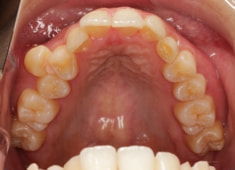

症例紹介

左上3番埋伏歯

治療法:フルパッシブブラケット:T21

治療前